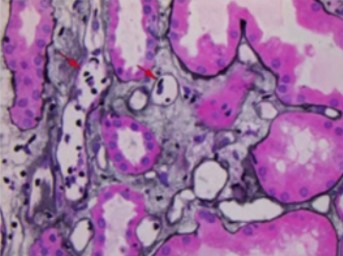

Results: Thirty-two years old Caucasian female with end stage kidney disease secondary to HIV infection underwent deceased-donor renal transplant in 2018 with KDPI 19% and cPRA 84%. Serum creatinine level had been stable at 1.1mg/dL to 1.2mg/dL post-transplant. This patient was monitored using AlloSure (CareDx) for 1-,2-,3-,4-,6- and 9-month post-transplant. AlloSure values for month 1 to 6 were <0.21, which indicates stable allograft function. However, at 9-month post-transplant, AlloSure value went up to 4.5%, which indicates possible allograft injury, while serum creatinine level remained stable at 1.2 mg/dL with low level of class 2 DSA (DR-1573). Despite stable creatinine level and low level DSA, we initiated biopsy because of sharp increase in AlloSure value. Biopsy revealed acute T-cell mediated rejection and acute vascular rejection. The second case is a 33 years-old Caucasian female with history of previous renal transplant. The first allograft failed in 2018 due to renal artery and vein thrombosis. The patient underwent deceased donor kidney transplant in 2019. Serum creatinine level was stable at 1.0 – 1.3 mg/dL and sharp increase in respectively. At month 3, AlloSure value went up to 0.78% but DSA was negative. We initiated biopsy based on increase in AlloSure value and it revealed acute antibody mediated rejection (ABMR) (Figure 1). The third case is a 56 years-old male with history of end-stage renal disease secondary to hypertension. The patient received deceased donor kidney transplant in 2017. He developed acute renal failure (Cr went up from 1.2 mg/dl to 1.7 mg/dL) few months after kidney transplant and his kidney biopsy showed acute antibody mediated rejection and T-cell mediated rejection which were treated. At 1-year post-transplant, serum creatinine level remained 1.2 mg/dL to 1.3 mg/dL. He was place on monthly Allosure surveillance. The first value was 1.9%, which indicate possible allograft injury. Monthly monitoring showed increase trend in AlloSure value up to 4.1% while Cr remained stable at 1.2 mg/dL-1.3 mg/dL. At that point, biopsy was performed, and it revealed acute antibody mediated rejection and chronic active antibody rejection. Patient was treated with for ABMR. In addition, monthly Tocilizumab was considered for chronic active antibody mediated rejection for 6 months. AlloSure values reflected the early detection of rejection in a patient with stable Cr as well as the efficacy of treatment with down trending values (Figure 2).